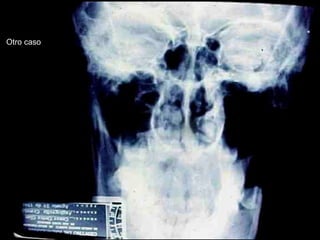

Queratoquiste odontogénico

Otro caso